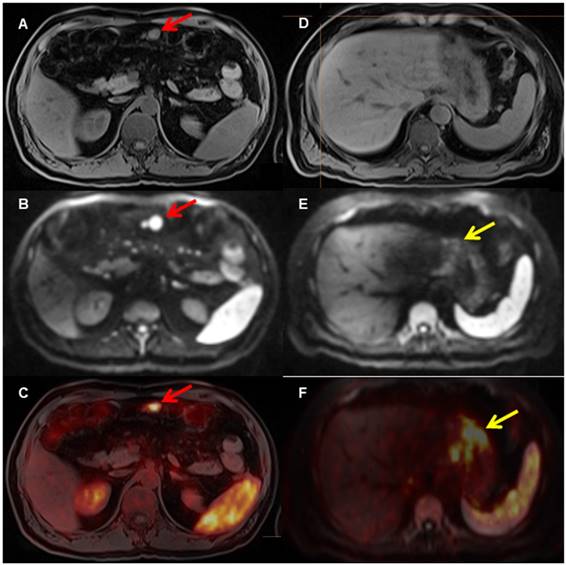

Figure 2

A patient with biopsy-proven gastric MALT lymphoma. The [68Ga]Pentixafor PET shows several areas in the stomach with increased [68Ga]Ga-Pentixafor uptake (F, yellow arrow on fused PET/MRI) and restricted diffusion on DWI (E, yellow arrow, D T1 VIBE Dixon), indicating the MALT lymphoma. In addition, there is evidence of an enlarged mesenteric lymph node (A, T1 with restricted diffusion on DWI b_800 (B, red arrow) and markedly increased uptake on PET (C, red arrow on fused PET/MRI), consistent with lymph node involvement.